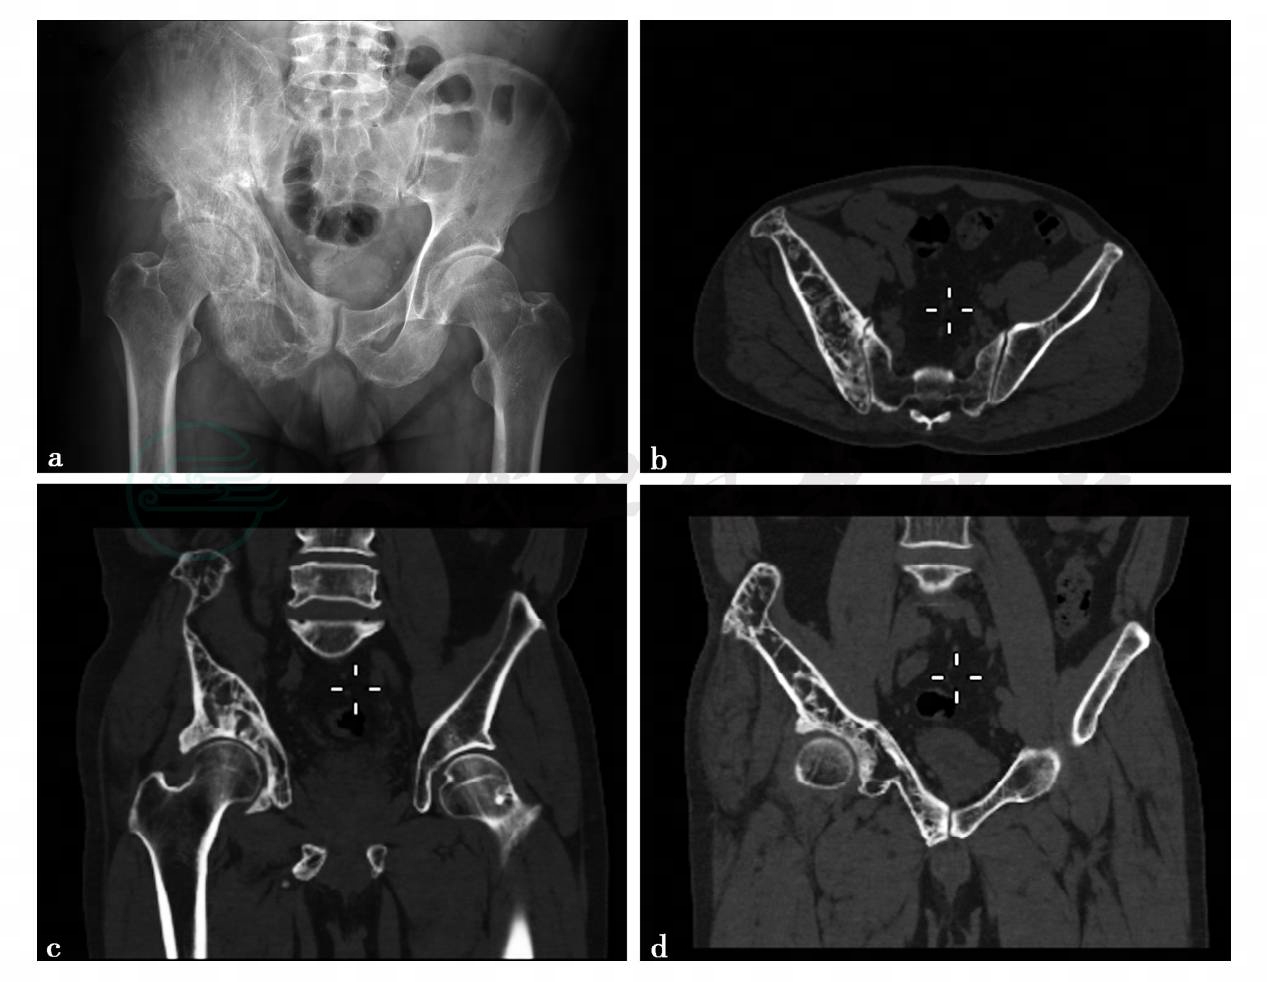

图1 图1a,骨盆正位示右侧髋臼骨质形态失常,骨小梁增粗。图1b~d,骨盆CT平扫(三维重建)示右侧髋骨形态失常,骨质硬化,骨小梁增粗、排列紊乱,髓腔扩大

病例1,畸形性骨炎。